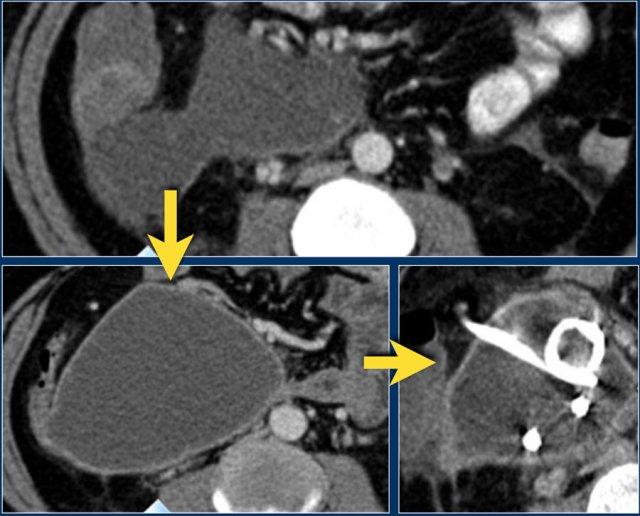

Các hình ảnh thuộc về một bệnh nhân viêm tụy cấp.

Trên hình ảnh phía trên là một ổ dịch ở vùng đầu tụy trong khoang cạnh thận trước bên phải.

Ở giai đoạn này, không thể phân biệt giữa ổ dịch quanh tụy cấp tính và ổ hoại tử cấp tính.

Trên phim chụp theo dõi, ổ dịch ở khoang cạnh thận trước bên phải tăng kích thước.

Ổ dịch có tỷ trọng dịch và thành mỏng ngấm thuốc.

Đây có thể là nang giả tụy hoặc ổ hoại tử được bao bọc, có thể nhiễm trùng hoặc không.

Bệnh nhân tiến triển nhiễm khuẩn huyết và được dẫn lưu qua da.

Sau dẫn lưu, kích thước ổ dịch hầu như không giảm.

Bệnh nhân được phẫu thuật và ổ dịch được phát hiện chứa đầy mảnh vụn hoại tử, điều này không được nhận ra trên CT, do đó đây là ổ hoại tử được bao bọc chứ không phải nang giả tụy.

Các mảnh vụn hoại tử quá đặc để có thể dẫn lưu qua da thành công.